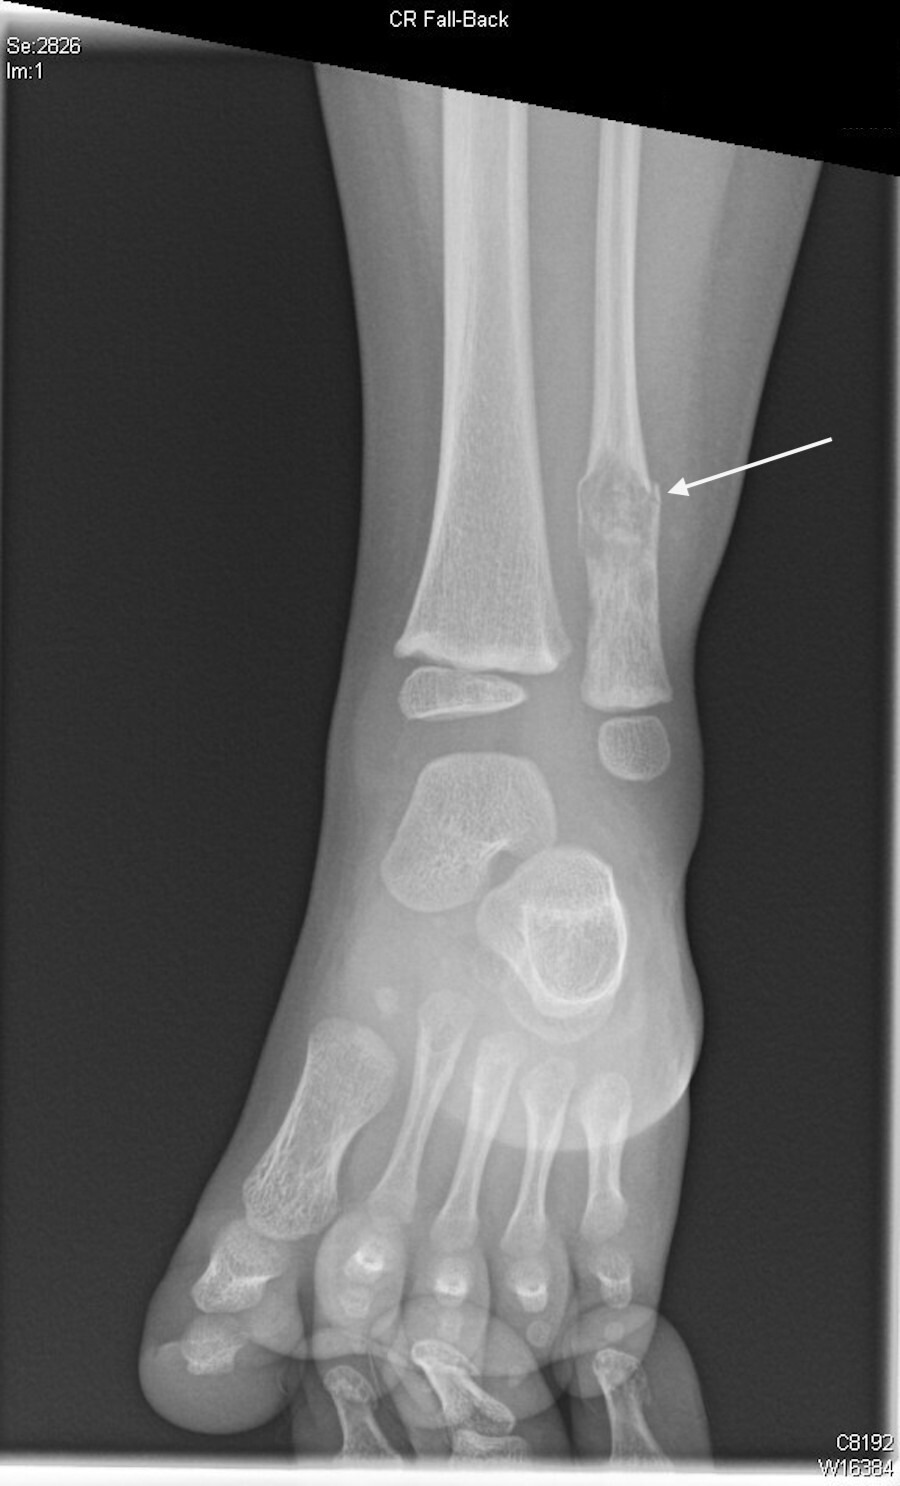

Imaging (CT scan) revealed a pathologic left fibular fracture [Figure 1].

An approximately 0.9 x 1 x 1.3 cm, ill-defined heterogeneous lytic lesion in the distal diaphysis of the left fibula was observed that caused the fracture [Figure 2].